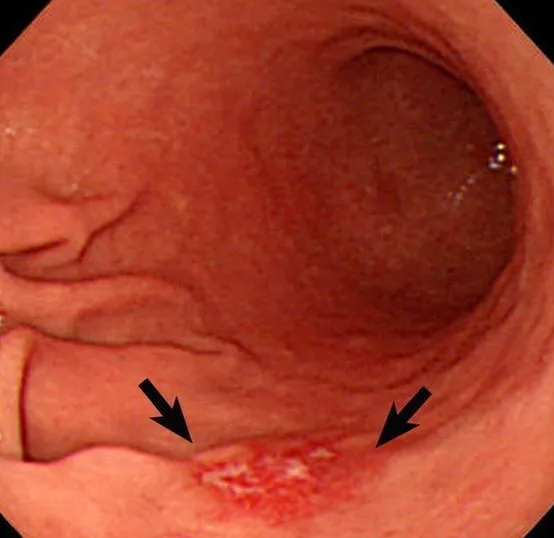

案例二:

王女士,女,53岁,银行职员,因“消化不良”就诊,在医生苦口婆心的劝说下,不情愿地做了胃镜。

胃底发现几处直径约0.5cmx0.3cm不等的糜烂灶,病理结果显示:印戒细胞癌。这是胃癌中之首恶,隐蔽、狡诈、凶险!

虽然经历了痛苦的治疗过程,也几乎花光了家里的所有积蓄,最终,王女士还是离开了心爱的丈夫和女儿,于半年后撒手人寰!